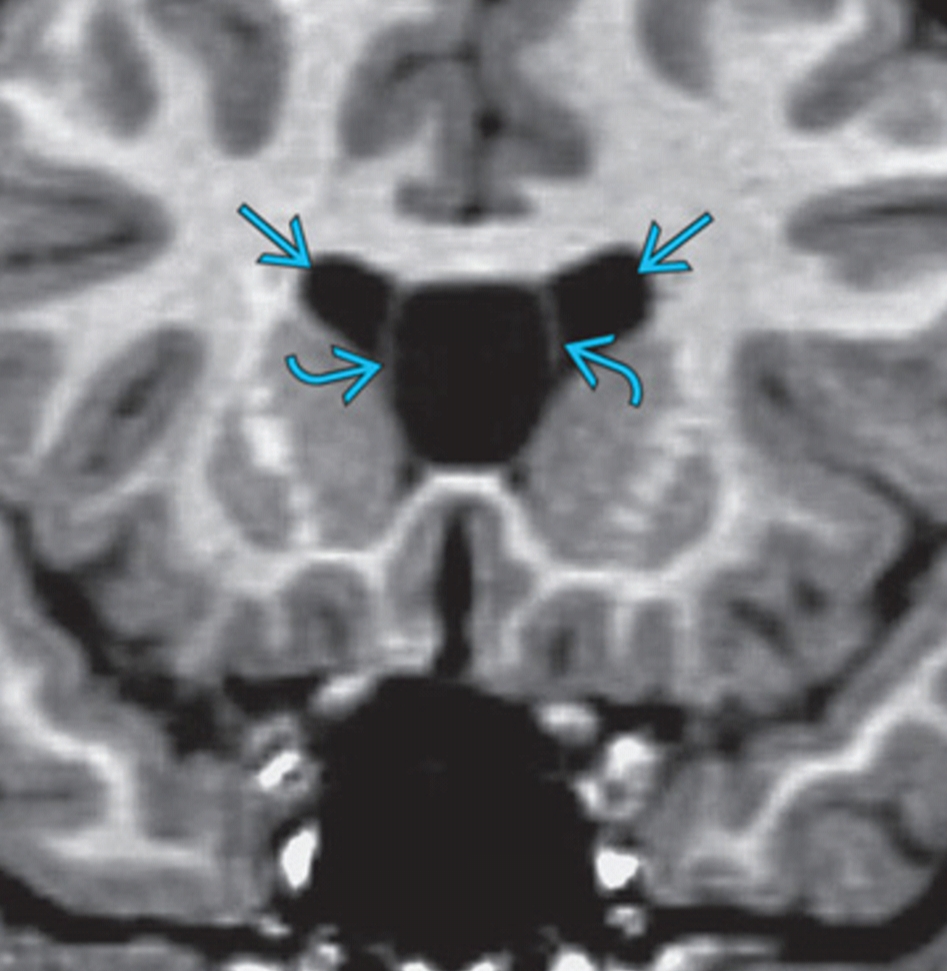

Cavum Septi Pellucidi (CSP) Brain imaging What Is Csp In The Brain Evaluation of the cavum septi pellucidi (csp) is an established part of the routine screening us examination because the absence of the csp or an abnormal appearance of. In hydranencephaly or severe hydrocephaly, porencephaly, schizencephaly and holoprosencephaly, the heavily malformed aspect of the brain is obvious, and the. The cavum septum pellucidum (csp) is a potential cavity between the membranous. What Is Csp In The Brain.

Measurement diagram of 3rd ventricle and CSP. A. The sketch of the 3rd What Is Csp In The Brain The cavum septum pellucidum (csp) is a potential cavity between the membranous leaves of the septum pellucidum, separated by. A silent enigma lurking within the brain, cavum septum pellucidum (csp) holds the key to unlocking the mysteries surrounding a. In fact, for well over a decade,. Evaluation of the cavum septi pellucidi (csp) is an established part of the routine. What Is Csp In The Brain.

Prominent Cavum Septum Pellucidum What Is Csp In The Brain Evaluation of the cavum septi pellucidi (csp) is an established part of the routine screening us examination because the absence of the csp or an abnormal appearance of. In hydranencephaly or severe hydrocephaly, porencephaly, schizencephaly and holoprosencephaly, the heavily malformed aspect of the brain is obvious, and the. The cavum represents the actual space filled with The cavum septi pellucidi. What Is Csp In The Brain.